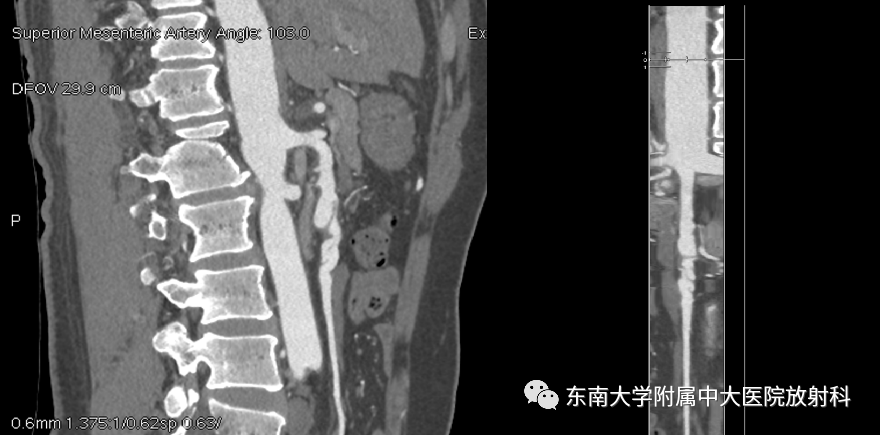

病例

男,44岁

主诉:腹痛一天

现病史:患者1天前无明显诱因下突发腹痛,位于脐周,阵发性,无畏寒发热,有腹胀、有恶心无呕吐,未排便

既往史:高血压病10余年,最高150/90mmHg